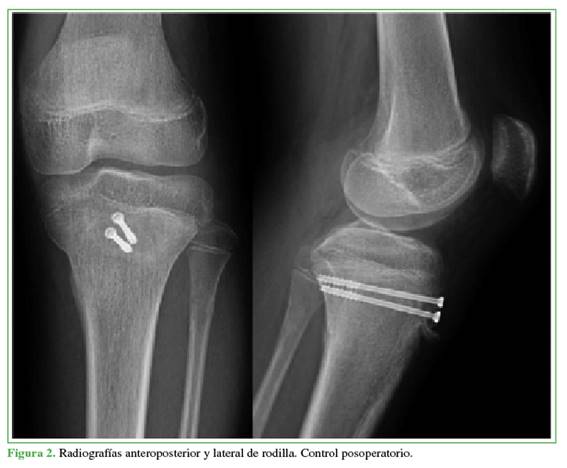

El paciente fue operado de urgencia y se lo sometió a reducción cerrada y osteosíntesis con dos tornillos percutáneos canulados de rosca parcial, de 3,5 mm de diámetro (Figura 2). El posoperatorio inmediato transcurrió sin incidencias. Se le permitió la carga parcial desde el inicio, con ortesis en extensión y flexión gradual desde 0° hasta 90º a partir de la tercera semana, junto con ejercicios de fortalecimiento cuadricipital progresivo asistido por un fisioterapeuta. A las 12 semanas, se autorizó la reincorporación a la actividad deportiva.